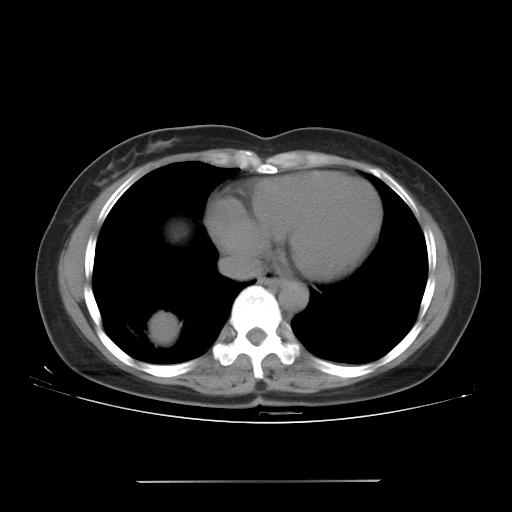

女 46岁,咳嗽咳血10月

【linyiming】右肺下叶见类圆形软组织影,边缘欠规整,略分叶状。考虑炎症假瘤可能?

【aosangwa】肺癌的主要特征是:毛刺征、分叶征及胸膜凹陷征,此病例位于右肺下叶距胸膜很近,但没有胸膜凹陷征,其周围像示渗出性病变,病灶在两窗上没有大小没有发生大小改变。

考虑其良性肿瘤,炎性假瘤可能性大,其主要鉴别是:结核球、周围型肺癌、血管瘤

病理诊断类癌(周围型)。